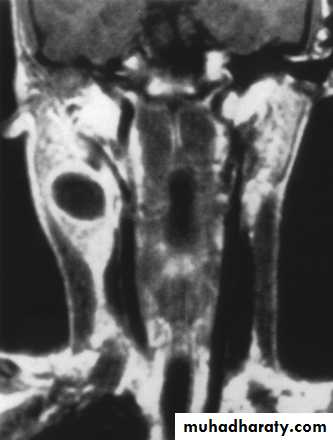

Branchial Cleft Cysts

Branchial cleft anomalies2nd cleft most common (95%) – tract medial to CnXII between internal and external carotid aa.

Most common as smooth, fluctuant mass underlying the SCM

Skin erythema and tenderness if infected

Treatment

Initial control of infection

Surgical excision, including tract